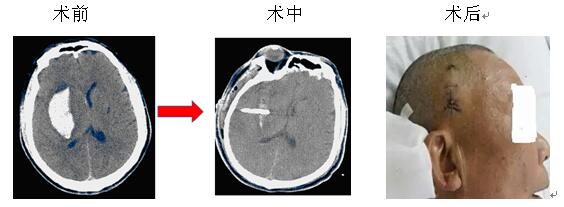

微創(chuàng)治療腦出血是指在CT或立體定向引導(dǎo)下,找到離血腫中心最近的位置,同時避開重要的組織,用YL-I型針管一體裝置在電驅(qū)動下安放引流管、抽吸血凝塊,減少血腫體積,達(dá)到清除血腫的目的。此方法創(chuàng)傷微小,操作快捷,費用較低,在有CT的醫(yī)療器械情況下即可實施,故對廣大病患,特別是老年多病的腦出血患者而言是一種不二的選擇。

院神經(jīng)內(nèi)科率先在衡陽地區(qū)實施微創(chuàng)治療腦出血,現(xiàn)經(jīng)救治的病患已達(dá)3000余人次,絕大部分患者得到好的結(jié)果,較少的死亡率,較輕的致殘率。本院將繼續(xù)提供較好的治療和服務(wù),來滿足病友的需求,也歡迎病友垂詢。